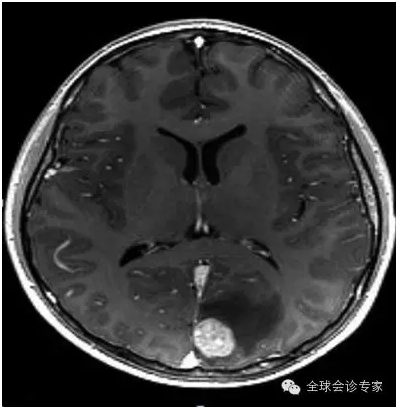

患者,65岁,男,2014年10月腹部不适、头疼检查,诊断为(1)高分化肝细胞癌,大小约250px,明显肝硬化。(2)脑转移瘤,左枕叶处大小约75px。(3)II型糖尿病,需要胰岛素治疗。(4)慢性肾病;(5)中度高血压,有心衰病史。

患者病情处于晚期,体内病灶巨大且有脑转移,不能实施外科手术治疗。经亨利福特医院专家组咨询,患者于2014年11月10日在美国亨利福特医院进行EDGE无创手术治疗。先后对肝脏肿瘤和脑转移瘤进行EDGE治疗,在医院共治疗8天。每个肿瘤每天治疗1次,每次治疗约10分钟左右,肝脏肿瘤共治疗6次,脑肿瘤治疗4次。

患者手术过程中无任何不适,每次治疗后正常回家。2015年5月回访,患者一般情况良好,体重明显增加。经影像检查,肝脏巨大肿瘤被彻底清除,脑部肿瘤几乎完全消除,且没有复发。生化检查,肝功能未见正常。

脑转转移瘤治疗前75px

脑转移瘤治疗后几乎完全消除